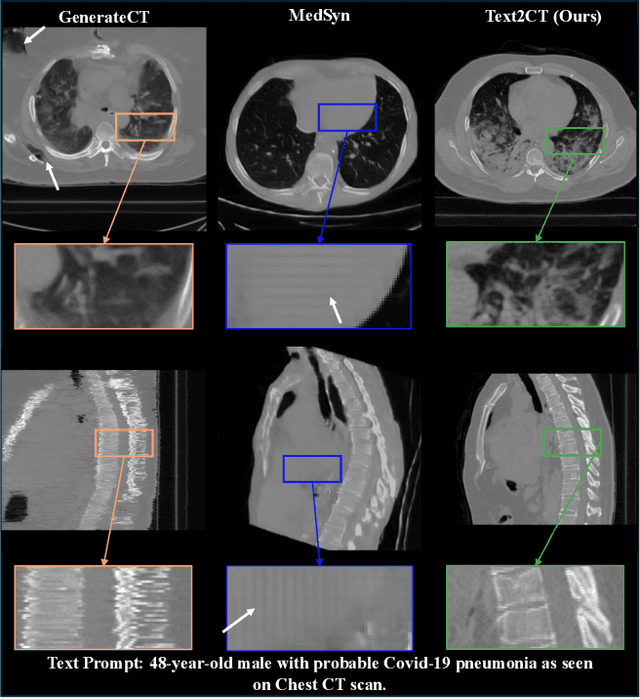

Abstract:Generating 3D CT volumes from descriptive free-text inputs presents a transformative opportunity in diagnostics and research. In this paper, we introduce Text2CT, a novel approach for synthesizing 3D CT volumes from textual descriptions using the diffusion model. Unlike previous methods that rely on fixed-format text input, Text2CT employs a novel prompt formulation that enables generation from diverse, free-text descriptions. The proposed framework encodes medical text into latent representations and decodes them into high-resolution 3D CT scans, effectively bridging the gap between semantic text inputs and detailed volumetric representations in a unified 3D framework. Our method demonstrates superior performance in preserving anatomical fidelity and capturing intricate structures as described in the input text. Extensive evaluations show that our approach achieves state-of-the-art results, offering promising potential applications in diagnostics, and data augmentation.